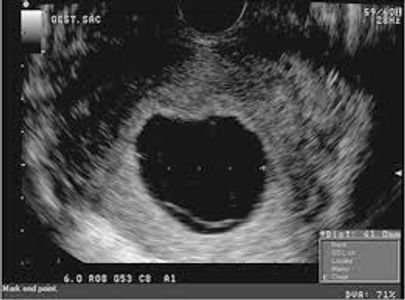

The chance of miscarriage decreases dramatically after 9 weeks if the embryo is normal in size with a normal heart beat by ultrasound. If a heartbeat is present between 6 and 9 weeks, then there is still a chance of early miscarriage. Ultrasound findings of a nonviable pregnancy vary with the stage of pregnancy that was achieved. These include

Other abnormal findings include irregular shape of the gestational sac, abnormal position (within the uterine cavity or low, indicating a miscarriage in progress), poor surrounding choriodecidual reaction, and abnormal internal morphology including an 'empty amnion'.